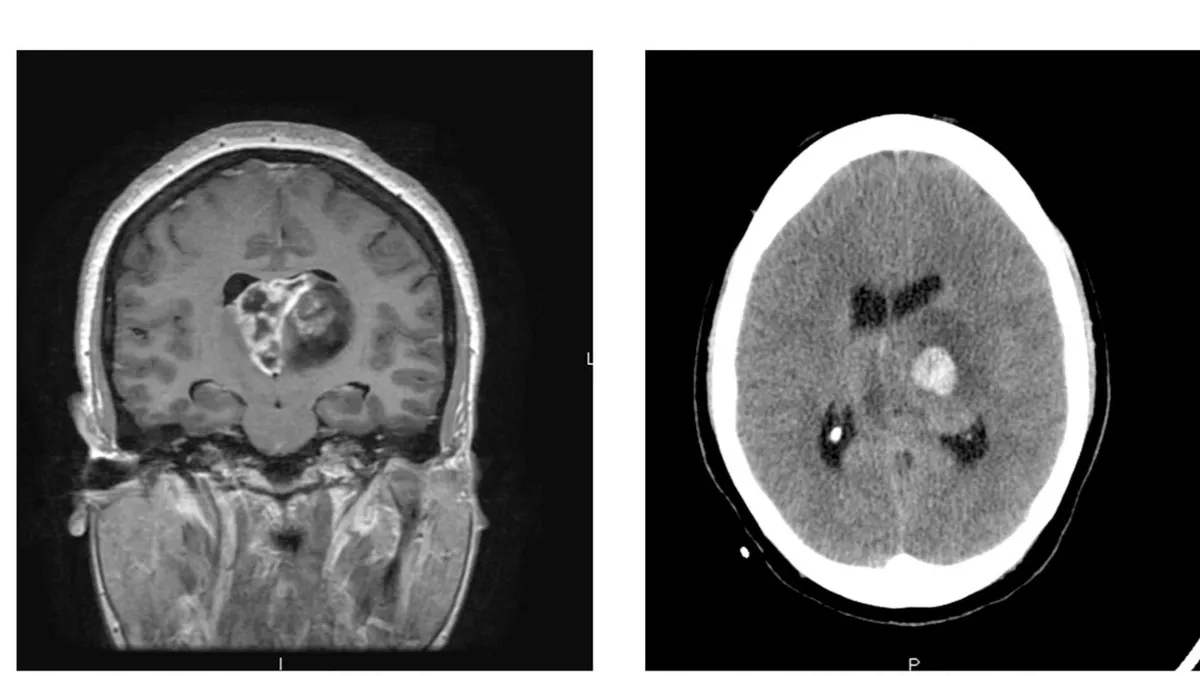

ويعد الورم الدبقي الأرومي من أكثر السرطانات عدوانية، إذ لا يتجاوز متوسط البقاء على قيد الحياة بعد التشخيص 14 شهراً، ولم يتحقق أي تقدم كبير في علاجه منذ عقود.

ومع محدودية الأدوية والخيارات المتاحة، يبحث العلماء عن طرق مبتكرة لفهم جذور المرض والتعامل معه من البداية.

ما هو الورم الأرومي الدبقي؟

- نوع من السرطان يبدأ في الدماغ أو الحبل النخاعي.

- يتكون من خلايا تُسمى "الخلايا النجمية" التي تدعم الخلايا العصبية.

- ينمو بسرعة وقد يغزو الأنسجة السليمة ويدمرها.

- يمكن أن يصيب أي عمر، لكنه أكثر شيوعًا لدى البالغين الأكبر سنًا.

- لا يوجد علاج شافٍ حتى الآن، لكن العلاجات تساعد على إبطاء النمو وتخفيف الأعراض.